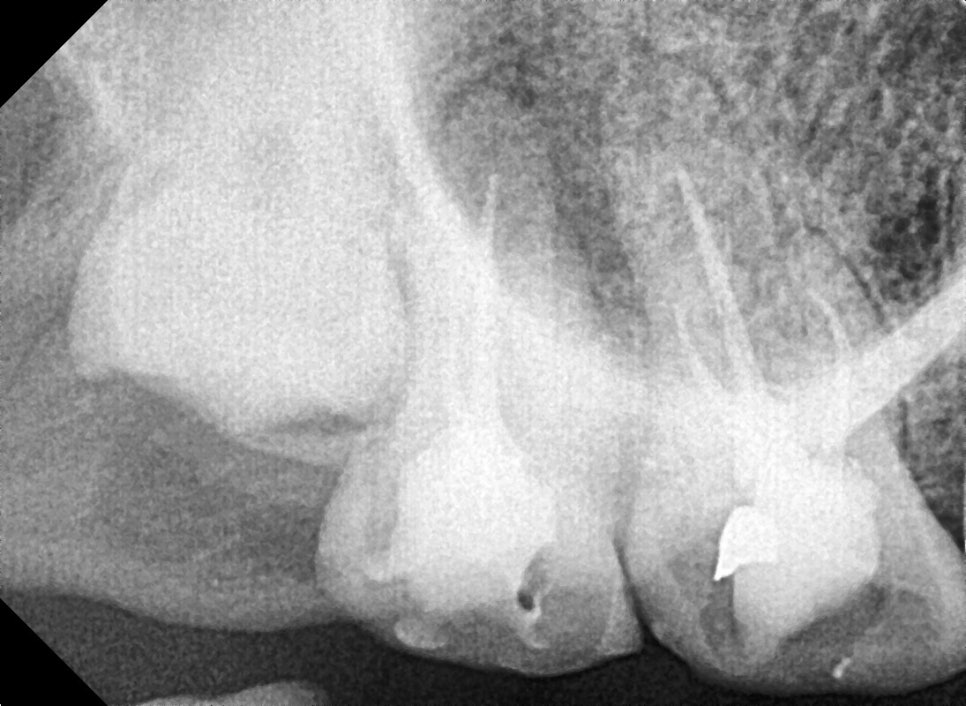

*MTA 적용 사례

사진이 뚜렷하게 잘 나온 다른 환자분 사진을 예시로 보여드리겠습니다.

뿌리 끝 염증 상태 (전)

치아 뿌리 염증 빼야 된다는 치아, 이렇게 살렸습니다. 치료 방법

아쉽게도 mta치료는 건강보험이 적용되지 않습니다.

하지만 실제 적용 사례들에서

뿌리 끝 염증 치유에 도움이 되어

필요한 경우 적절하게 사용하면 치료 결과를 높일 수 있습니다.

1개월 후 경과 확인

환자분의 강한 치료 의지와 저의 노력 덕분일까요?

250220

염증이 점차 가라앉으면서 치아가 안정되기 시작했습니다.

흔들림도 눈에 띄게 줄어들었습니다.

최종적으로 보철물(크라운)까지 씌워드렸고, 현재는 건강하게 사용하고 계십니다.

250220 치아 뿌리 염증 빼야 된다는 치아, 이렇게 살렸습니다. 치료 방법